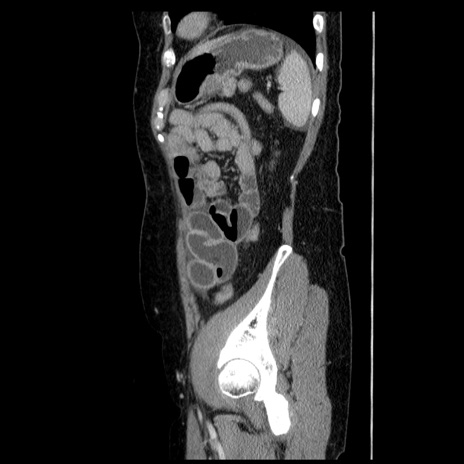

横断像

【症例】50歳代女性

【主訴】下腹部痛

【現病歴】本日朝より下痢2回あり。 昼食を食べた後、嘔吐3回、下腹部痛認め、症状軽快せず、当院救急搬送。

最終食事:本日昼(生ものなし)。 昨日の夜、刺身を食ぺたとのこと。周囲に同様の症状の者なし。普段、排便は毎日あるとのこと。

【既往歴】卵巣癌術後(8年前に当院で卵巣摘出)

【身体所見】 意識清明、腹部:平坦、腸蠕動音→、やや硬、下腹部自発痛・圧痛あり、反跳痛あり、筋性防御なし。

【データ】WBC 16000、CRP 0.01